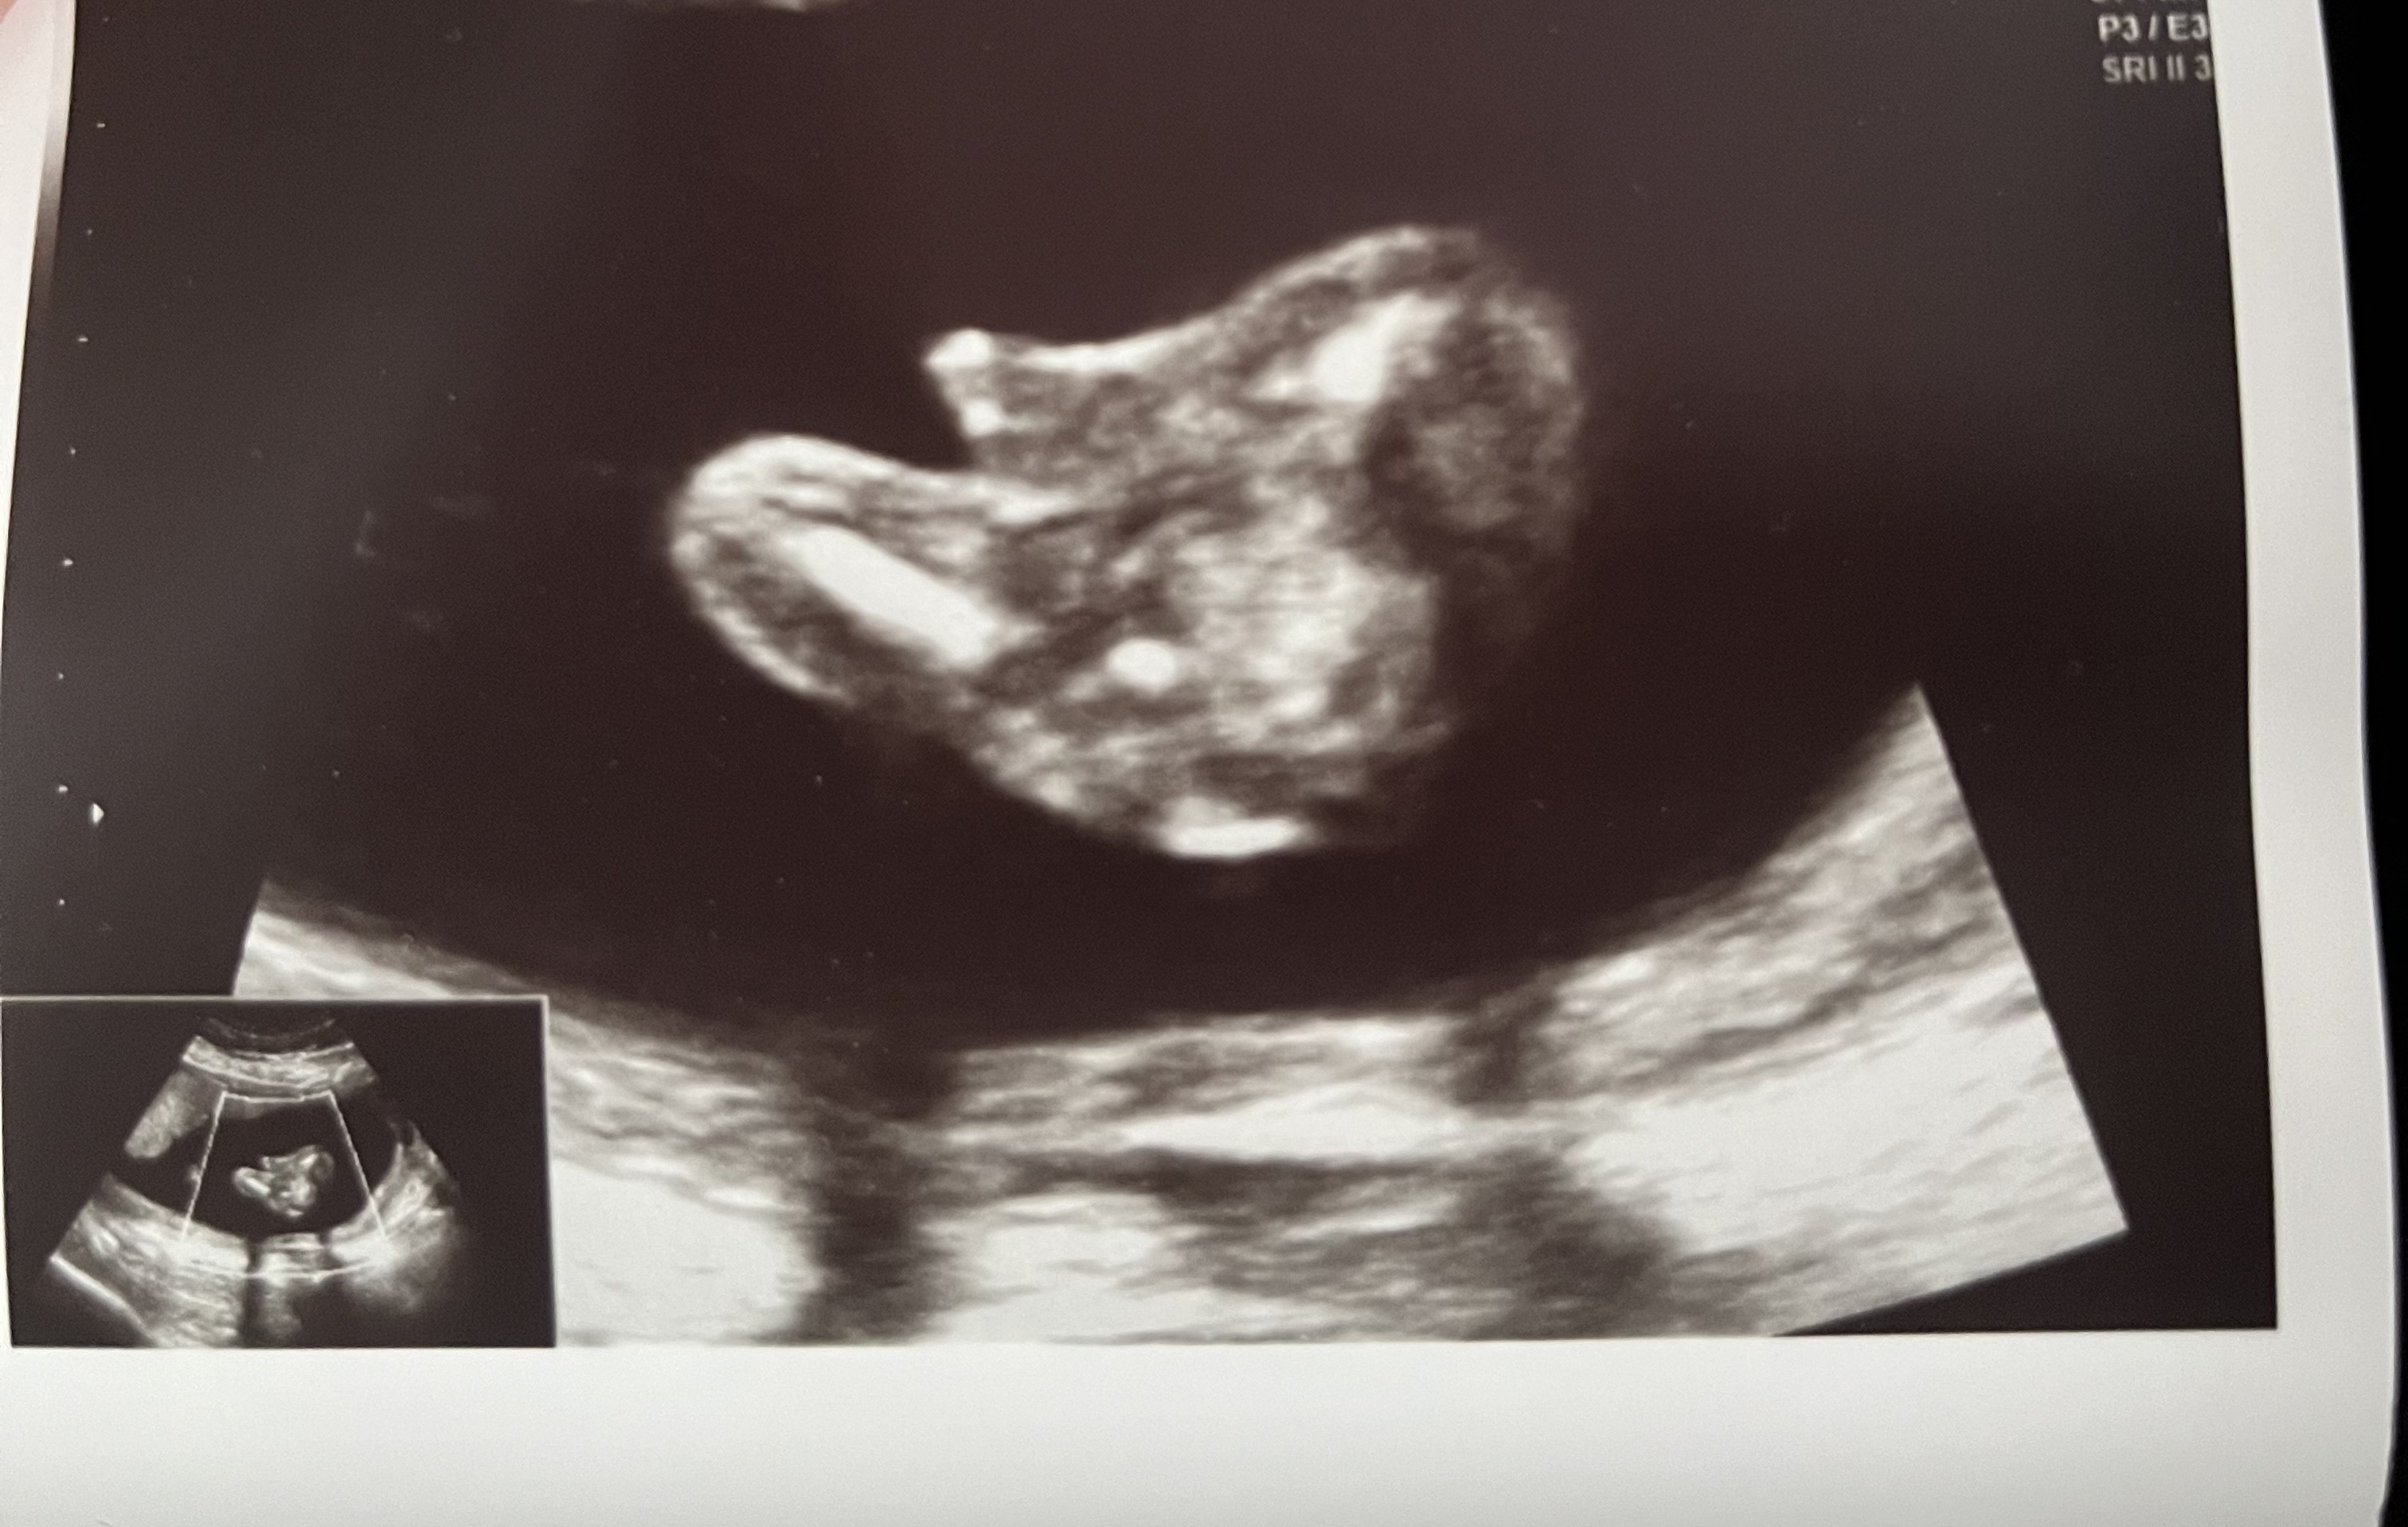

Cześć dziewczyny. Od początku ciąży zarówno lekarz z prenatalnych jak i mój lekarz mowią ze bedzie dziewczynka. Na 2 prenatalnych lekarz powiedział ze dziecko zle ułożone ale wydaje mu się ze chlopczyk. Teraz 26 tydzień. Moja lekarka mowi bez wątpliwości, że widzi wargi sromowe. Za 2 tyg mam 3 prenatalne ale ciekawość mnie zżera. Co myślicie o tym? Czy to faktycznie mogą być wargi? :) położna twierdzi ze na zdjęciu z prenatalnych to bardziej pepowina niż siusiak

U nas siusiak i jajeczka były wyraźnie widoczne, nawet jak maluch pchał tam rączki to nie było wątpliwości, bo to ładnie widać. Tutaj stawiam na dziewczynkę, bo ja nie widzę ani siusiaka ani jajeczek 😜

Na poprzednim zdjęciu eweidentnie widać wargi sromowe, myśle że zdjęcie z 24 tyg musi przedstawiać pępowine :) na 1 prenatalnym lekarz określił płeć?